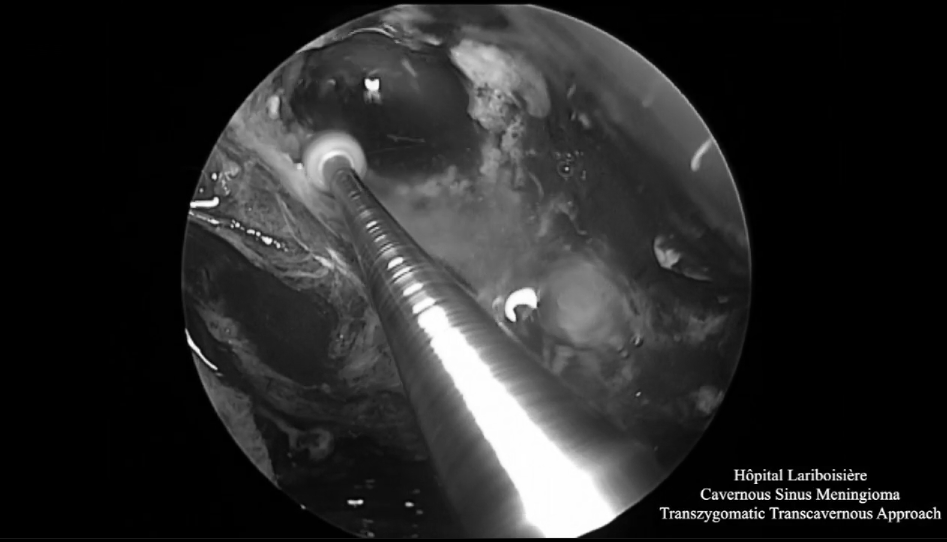

▼神經(jīng)內(nèi)鏡操作下暴露和切除腫瘤

神經(jīng)內(nèi)鏡操作下暴露和切除腫瘤